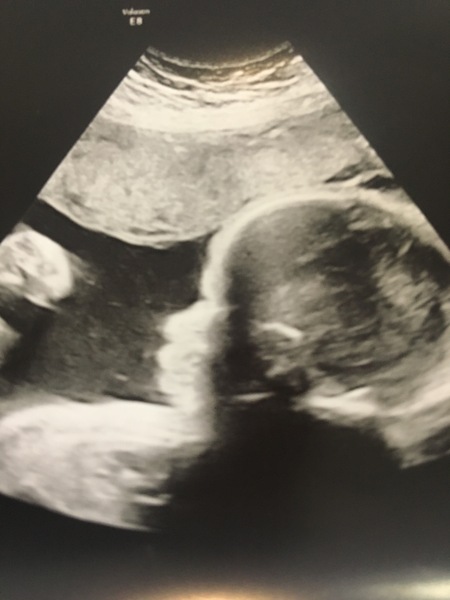

Scan went well! He’s measuring big at 3lb7 (29 weeks) so need to have more bloods done to check it’s not GD again but they arent concerned... been told again that we’ll just have big hairy babies haha! Saw he has lots of hair again which gives me all the feels, Lily had such gorgeous hair!!

@Anon20something what a fabulous scan photo. X

What a lovely picture @Anon20something its so clear! How lovely. I'd love my baby to have a head of hair!! Can they see that on the scan then?!

@Whiffle77 they spotted Lily’s hair on my 28 week scan last time, you could see little tufts today which was lovely!

@Anon20something Beautiful pic! And great on the head of hair. Super cute.

@Anon20something that's beautiful! And it made my heart melt to think of the hair too! Those memories of Lily must be so precious to you. I'm pleased it looks like you have another big, gorgeous, hairy baby on the way! xxx

@Anon20something Lovely scan photo x